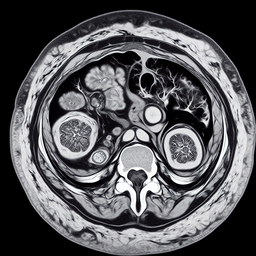

Магнітно-резонансна томографія (МРТ) матки та шийки матки є важливим неінвазивним методом діагностики, що надає детальну інформацію про стан цих органів. Процедура допомагає виявити різні патології, такі як пухлини, кісти або запальні процеси. МРТ використовує магнітні поля та радіохвилі для створення чітких зображень тканин.